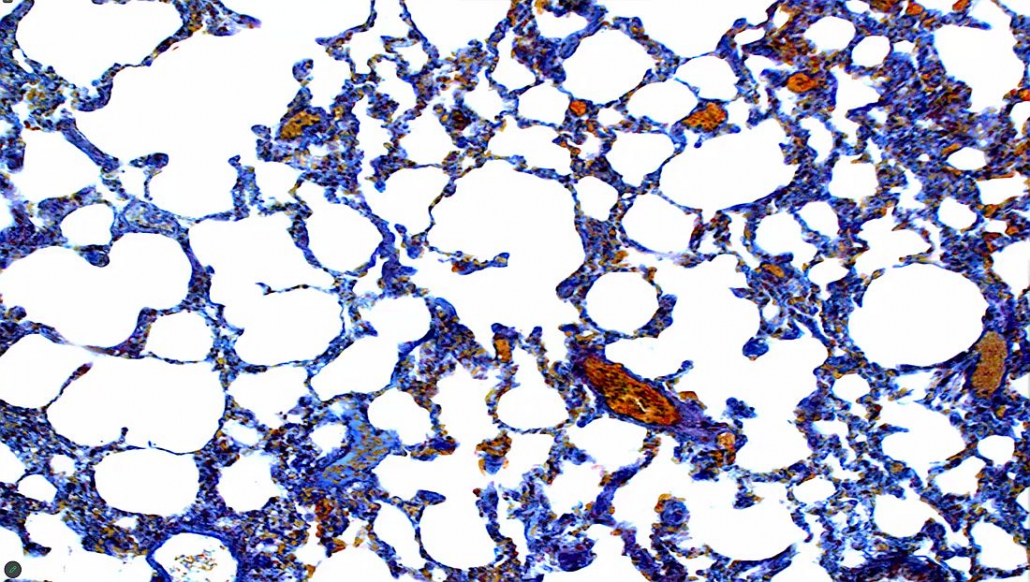

- Der Pilz Aspergillus fumigatus in einer Lunge ist tödlich, wenn das Immunsystem schwach ist. Nur bei entsprechender Färbung (welche war das noch?) sichtbar.